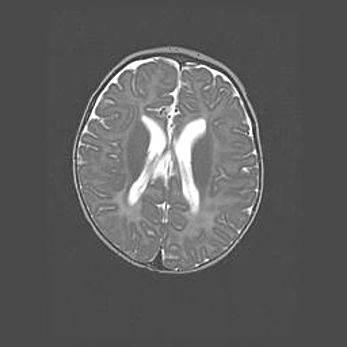

Лейкомаляция с кистозно-глиозной дегенерацией головного мозга.

Возраст: 2 месяца 25 дней

Вес: 6400 г

Окружность головы: 40 см

Срок гестации: 41 неделя

Лейкомаляцию относят к ишемически-гипоксическим повреждениям головного мозга, диагностируемым у новорожденных. При лейкомаляции в головном мозге обнаруживают очаги некроза, возникшие после тяжелой гипоксии и нарушения кровотока. В процессе морфогенеза очаги проходят три стадии: 1) развития некроза, 2) резорбции и 3) формирования глиозного рубца или кисты. Перивентрикулярная лейкомаляция (ПЛ) встречается примерно в 12% случаев среди новорожденных, обычно – у недоношенных детей, причем, частота ее зависит от массы, с которой младенец появился на свет. Наибольшее число малышей страдает лейкомаляцией, если масса при рождении 1500-2500 г.